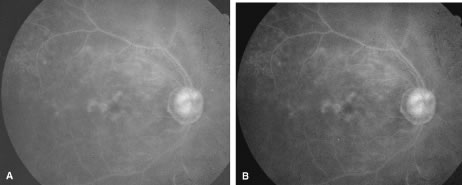

The ARN patient typically presents with progressive visual blurring in one or both eyes occurring over several weeks. These patients often are initially treated with corticosteroids, antitoxoplasmosis drugs, and other medications before arriving at the correct diagnosis. Examination reveals a prominent anterior uveitis that may be granulomatous or nongranulomatous (Fig. 1). Inflammatory signs may be prominent and cause severe pain (Fig. 2). The uveitis may be diffuse and so severe that it causes proptosis. These signs, and the diffuse vitreitis that makes the view of the retina difficult, may contribute to the high degree of delayed and/or misdiagnosis that occurs in the early stages of the disease. Significant vitreous cellular infiltration is seen in the presence of retinitis that is manifest by opacification of the retina, often most prominently in the periphery. Posterior pole involvement may include retinitis, as well as inflammation of the optic nerve head. Optic neuropathy might be the first sign of ARN with subsequent development of other retinal manifestations.8 Ultrasonography and computed tomography (CT) might be helpful in cases of ARN associated with optic nerve edema revealing enlargement of the optic nerve sheath.9 Even in ARN patients who are not immunocompromised and who have no clinical evidence of encephalitis, magnetic resonance imaging of selected cases has shown lesions of the lateral geniculate, optic tracts, and chiasma, which suggests that the virus spreads through the central nervous system (CNS) by axoplasmic transport from the retinal ganglion cells.10 A secondary retinal vasculitis is common, often accompanied by a mild number of retinal hemorrhages. Days to weeks after onset of the infection, the discrete peripheral lesions typically coalesce into a white or yellow ring of infected retina, and the associated vasculature is obliterated (Fig. 3). Necrotic retina desquamates into the vitreous resulting in vitreous sheets.3,6 Eventually, most untreated eyes can be expected to develop retinal detachment resulting from development of multiple full-thickness retinal breaks accompanied by traction or exudation.11 Giant retinal pigment epithelial tears have also been reported.12